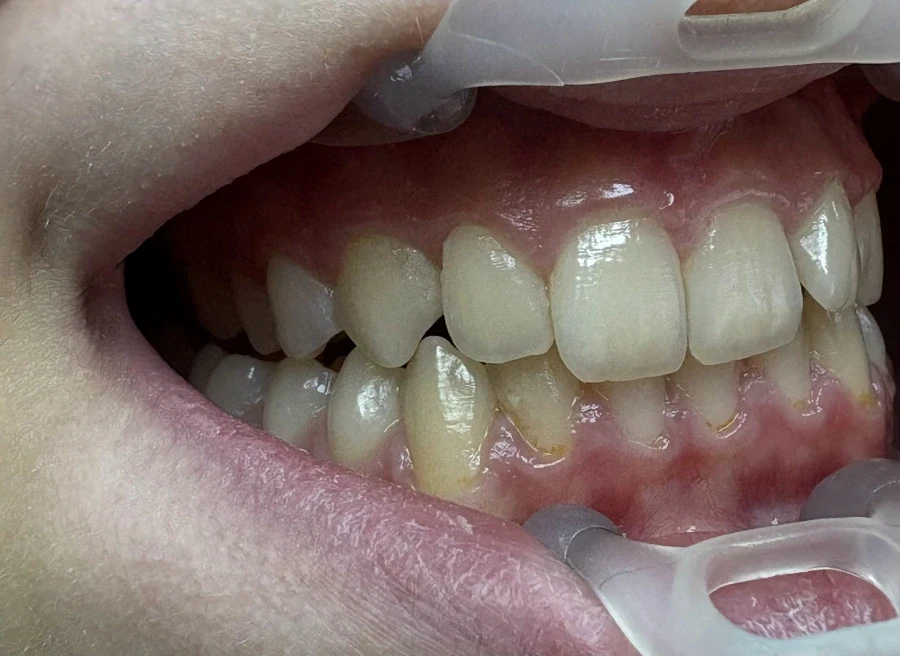

Стрипинг

Serviciul a fost efectuat la Дентално студио ТОП ДЕНТАЛ de томи пелова pe 9 Okt., 25